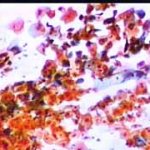

Papanicolaou: Πλακώδη επιθηλιακά κύτταρα κυρίως της επιφανειακήςστιβάδας, περίπου κατά50% και πλέον οξεόφιλα (16η ημέρα κύκλου!) . Ωστόσσο και αρκετά της διαμέσου και της παραβασικής, εν μέρει με διογκωμένους, ανισομεγέθειςαρραιοχρωματικούςδιαυγείςπυρήνεςKοιλοκυττάρωση.Η εικόνα συνηγορεί για δυσπλασία σοβαρού βαθμού.

Λόγω και του κολποσκοπικούευρήματος, μικροβιοψία που κατεδειξε ιστολογικώς CIN III